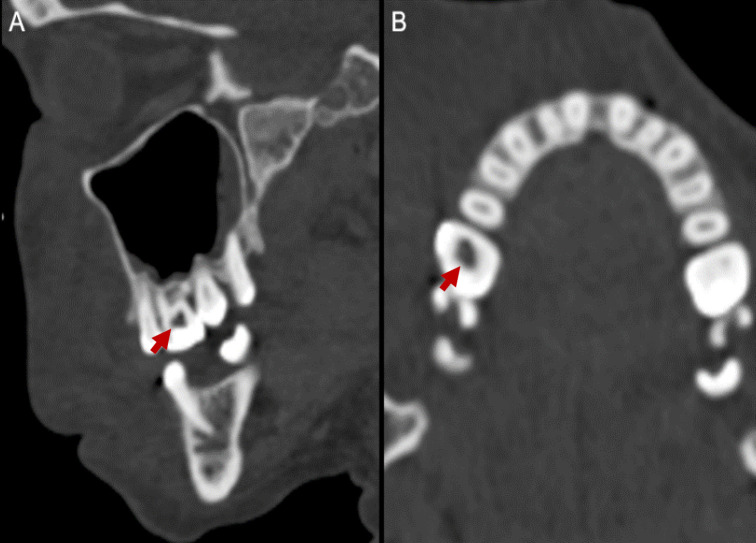

This case report highlights a rare complication of root canal treatment involving the inadvertent extrusion of sodium hypochlorite solution, resulting in a sodium hypochlorite-induced facial hematoma. A 44-year-old female patient presented significant right hemifacial swelling and ecchymosis following root canal therapy. Computed tomography imaging confirmed a hematoma involving the facial region without active signs of bleeding. Sodium hypochlorite, a potent cytotoxic agent commonly used in root canal procedures, was identified as the causative agent. Treatment consisted of prednisone, antibiotics, and NSAIDs, resulting in gradual improvement over a month. The cytotoxic properties of sodium hypochlorite, its variable concentrations, and risk factors associated with facial hematomas are discussed. It is essential to emphasize the rarity of such hematomas and highlight the need for precise technique, vigilant monitoring, and interdisciplinary collaboration to mitigate risks and prioritize patient safety.